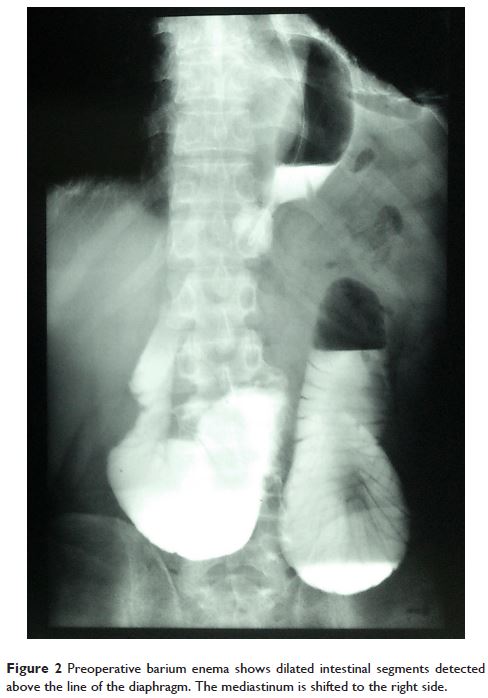

Case Report

- 作者:Yanlai Sun, Lei Yin, Hongfan Xue, Haipeng Wang, Zengjun Li, Jinming Yu

- 期刊:Therapeutics and Clinical Risk Management